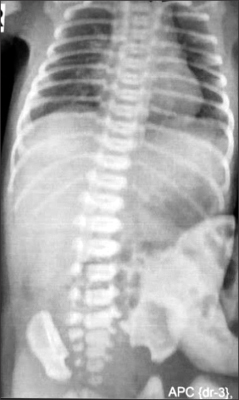

Fig. 2). The baby was taken up for surgery after adequate resuscitation. Intra-operatively, the sac contained few loops of small intestine. There was a fusiform SDI, about 25 cm proximal to the ileocecal valve. Note was made of conspicuous mesenteric vessels or mesenteric folds in a V-shaped pattern towards the two ends of the SDI (

Fig. 3). Resection and end to end anastomosis was done along with the abdominal wall repair. The child had an uneventful recovery and was discharged on postoperative day 7. The histopathology of the segment revealed normal ganglion cells and hypertrophy of muscle fibres.

The presence of mesenteric folds, abnormal mesenteric vessels demarcating the two ends of the dilated segment also suggest the presence of an erstwhile duplicated segment with its blood supply, which eventually got resorbed. This abnormal folds/vessel in the mesentery have been noted by some authors and is evident on some of the photographs in previous published articles [

45].

Fig. 3Intraoperative photograph shows segmental dilatation of the ileum (SDI). Black arrows depict the mesenteric bands/vessels in V-shaped pattern at ends of SDI.